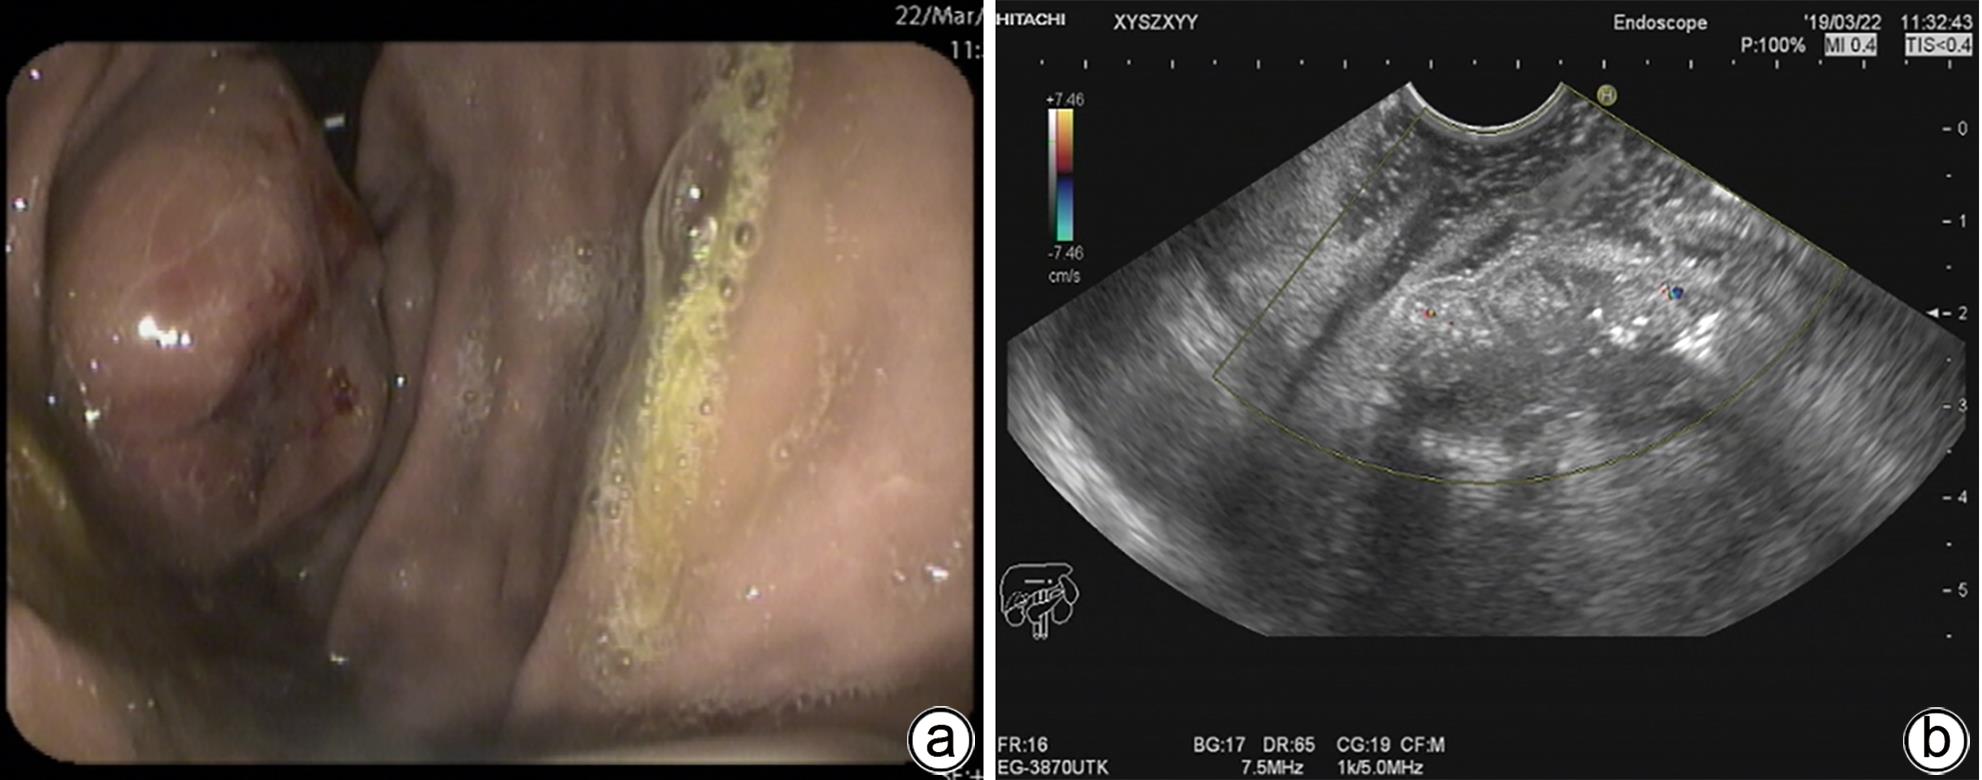

1例胆囊肿物患者,曾出现一过性黄疸,经腹部超声、增强CT、MRCP及PET-CT检查,均诊断为胆囊癌。手术探查见胆囊增大,胆囊颈部肿物挤压肝门部,但没有肿瘤侵犯表现,肝脏未见肿瘤转移征象,仅为患者行胆囊切除术。病理诊断为胆囊管状腺瘤,未见癌变。本病例特点是胆囊肿瘤巨大,影像未见肿瘤边缘浸润,病理未见恶变。